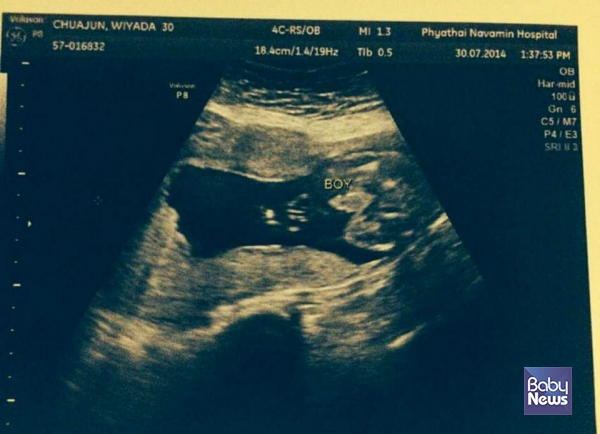

출산 당일, 부부는 대리모가 있는 태국으로 향했다. 아기는 제왕절개 분만으로 태어날 예정이었다. 부부는 마음을 졸이며 아이를 기다렸다. 잠시 후, 의사의 호출을 받고 탯줄을 자르기 위해 분만실로 들어갔다. 그런데 예기치 못한 일로 쫓겨났다.

"나중에 들었는데 아기에게 약간의 출혈이 있었다고 했어요. 분만실에서 의사들이 우왕좌왕하더라고요. 다른 의사도 더 들어오고.. 그래서 탯줄을 못 자르고 나오게 됐어요. 지금 생각하니 그게 제일 아쉽네요. 평생 한 번 있는 일이었는데..."

다행히 아기는 이상이 없었다. 결국, 신생아실에서 아기를 처음 안았다. 그는 아기와의 첫 만남을 떠올리며 '솔직히 특별한 느낌이 없었다'고 털어놨다. 평소에 가지고 있던 출산에 대한 환상과 현실이 너무 다르기도 했지만, 물리적으로 아기가 대리모의 뱃속에 있었던 열 달을 함께 하지 못했기 때문에 당연한 일이기도 했다.

"아기가 까맣고 쪼글쪼글하더라고요. 조금 낯설었어요. 특히 피부가 너무 까매서 처음에는 '내 아기가 아닌가?'라는 의심도 들더라고요. 행복해야 할 출산이었는데, 분만실서 목격한 사고 때문에 의료진에 대한 의심만 가득했죠. 지금 생각해 보면 출산에 대한 경험이 전혀 없었기 때문에 든 생각 같아요. 막 태어난 신생아는 저도 처음 본 거니까요."